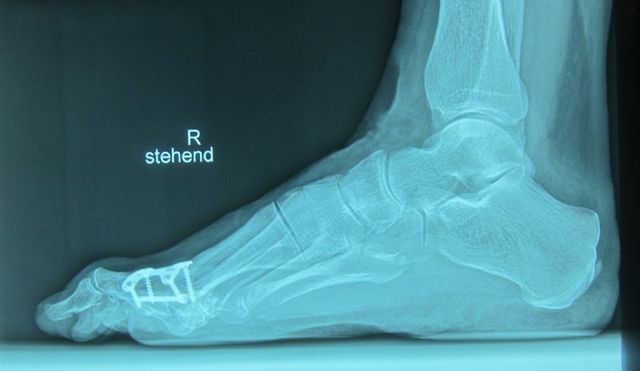

Versteifung

This is a dorsal plate and for further stabilisation we use an oblique plantar screw. In most cases it is not necessary to remove the hardware lateron.

Below you see a slimmer type of ostesynthesis material, which we use now:

The blue arrow shows the area of the former destroyed joint (Arthrosis). Now, after joint synthesis, there is a new built solid bone. The foot can be loaded and sports are possible without any pain. The foot is in an excellent shape.